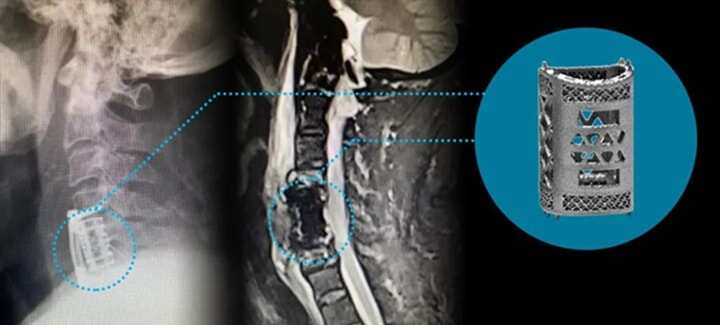

3D打印多孔型椎體融合器成功應(yīng)用于頸椎前路椎體次全切手術(shù)

2022年9月22日,湘雅常德醫(yī)院脊柱外科陳芳田主任團(tuán)隊(duì)成功完成一例頸椎間盤(pán)髓核切除術(shù)+C5椎體部分切除術(shù)+頸椎前路椎管減壓術(shù)+脊髓神經(jīng)根探查術(shù)+3D打印多孔型椎體融合器置入術(shù)。